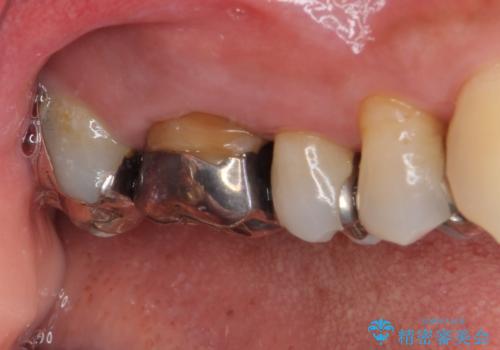

- 右上の小臼歯部に咬んだときに強い痛みを感じるとのことで来院された患者様です。

診査を行った結果、根管治療を行った後にオールセラミッククラウンにて補綴する治療計画となりました。

咬んだときの痛みに加えて夜間のズキズキする痛みもありましたが、1回目の根管治療実施後間もなく咬んだときの痛みがなくなったので、2回目に根管充填を行いました。